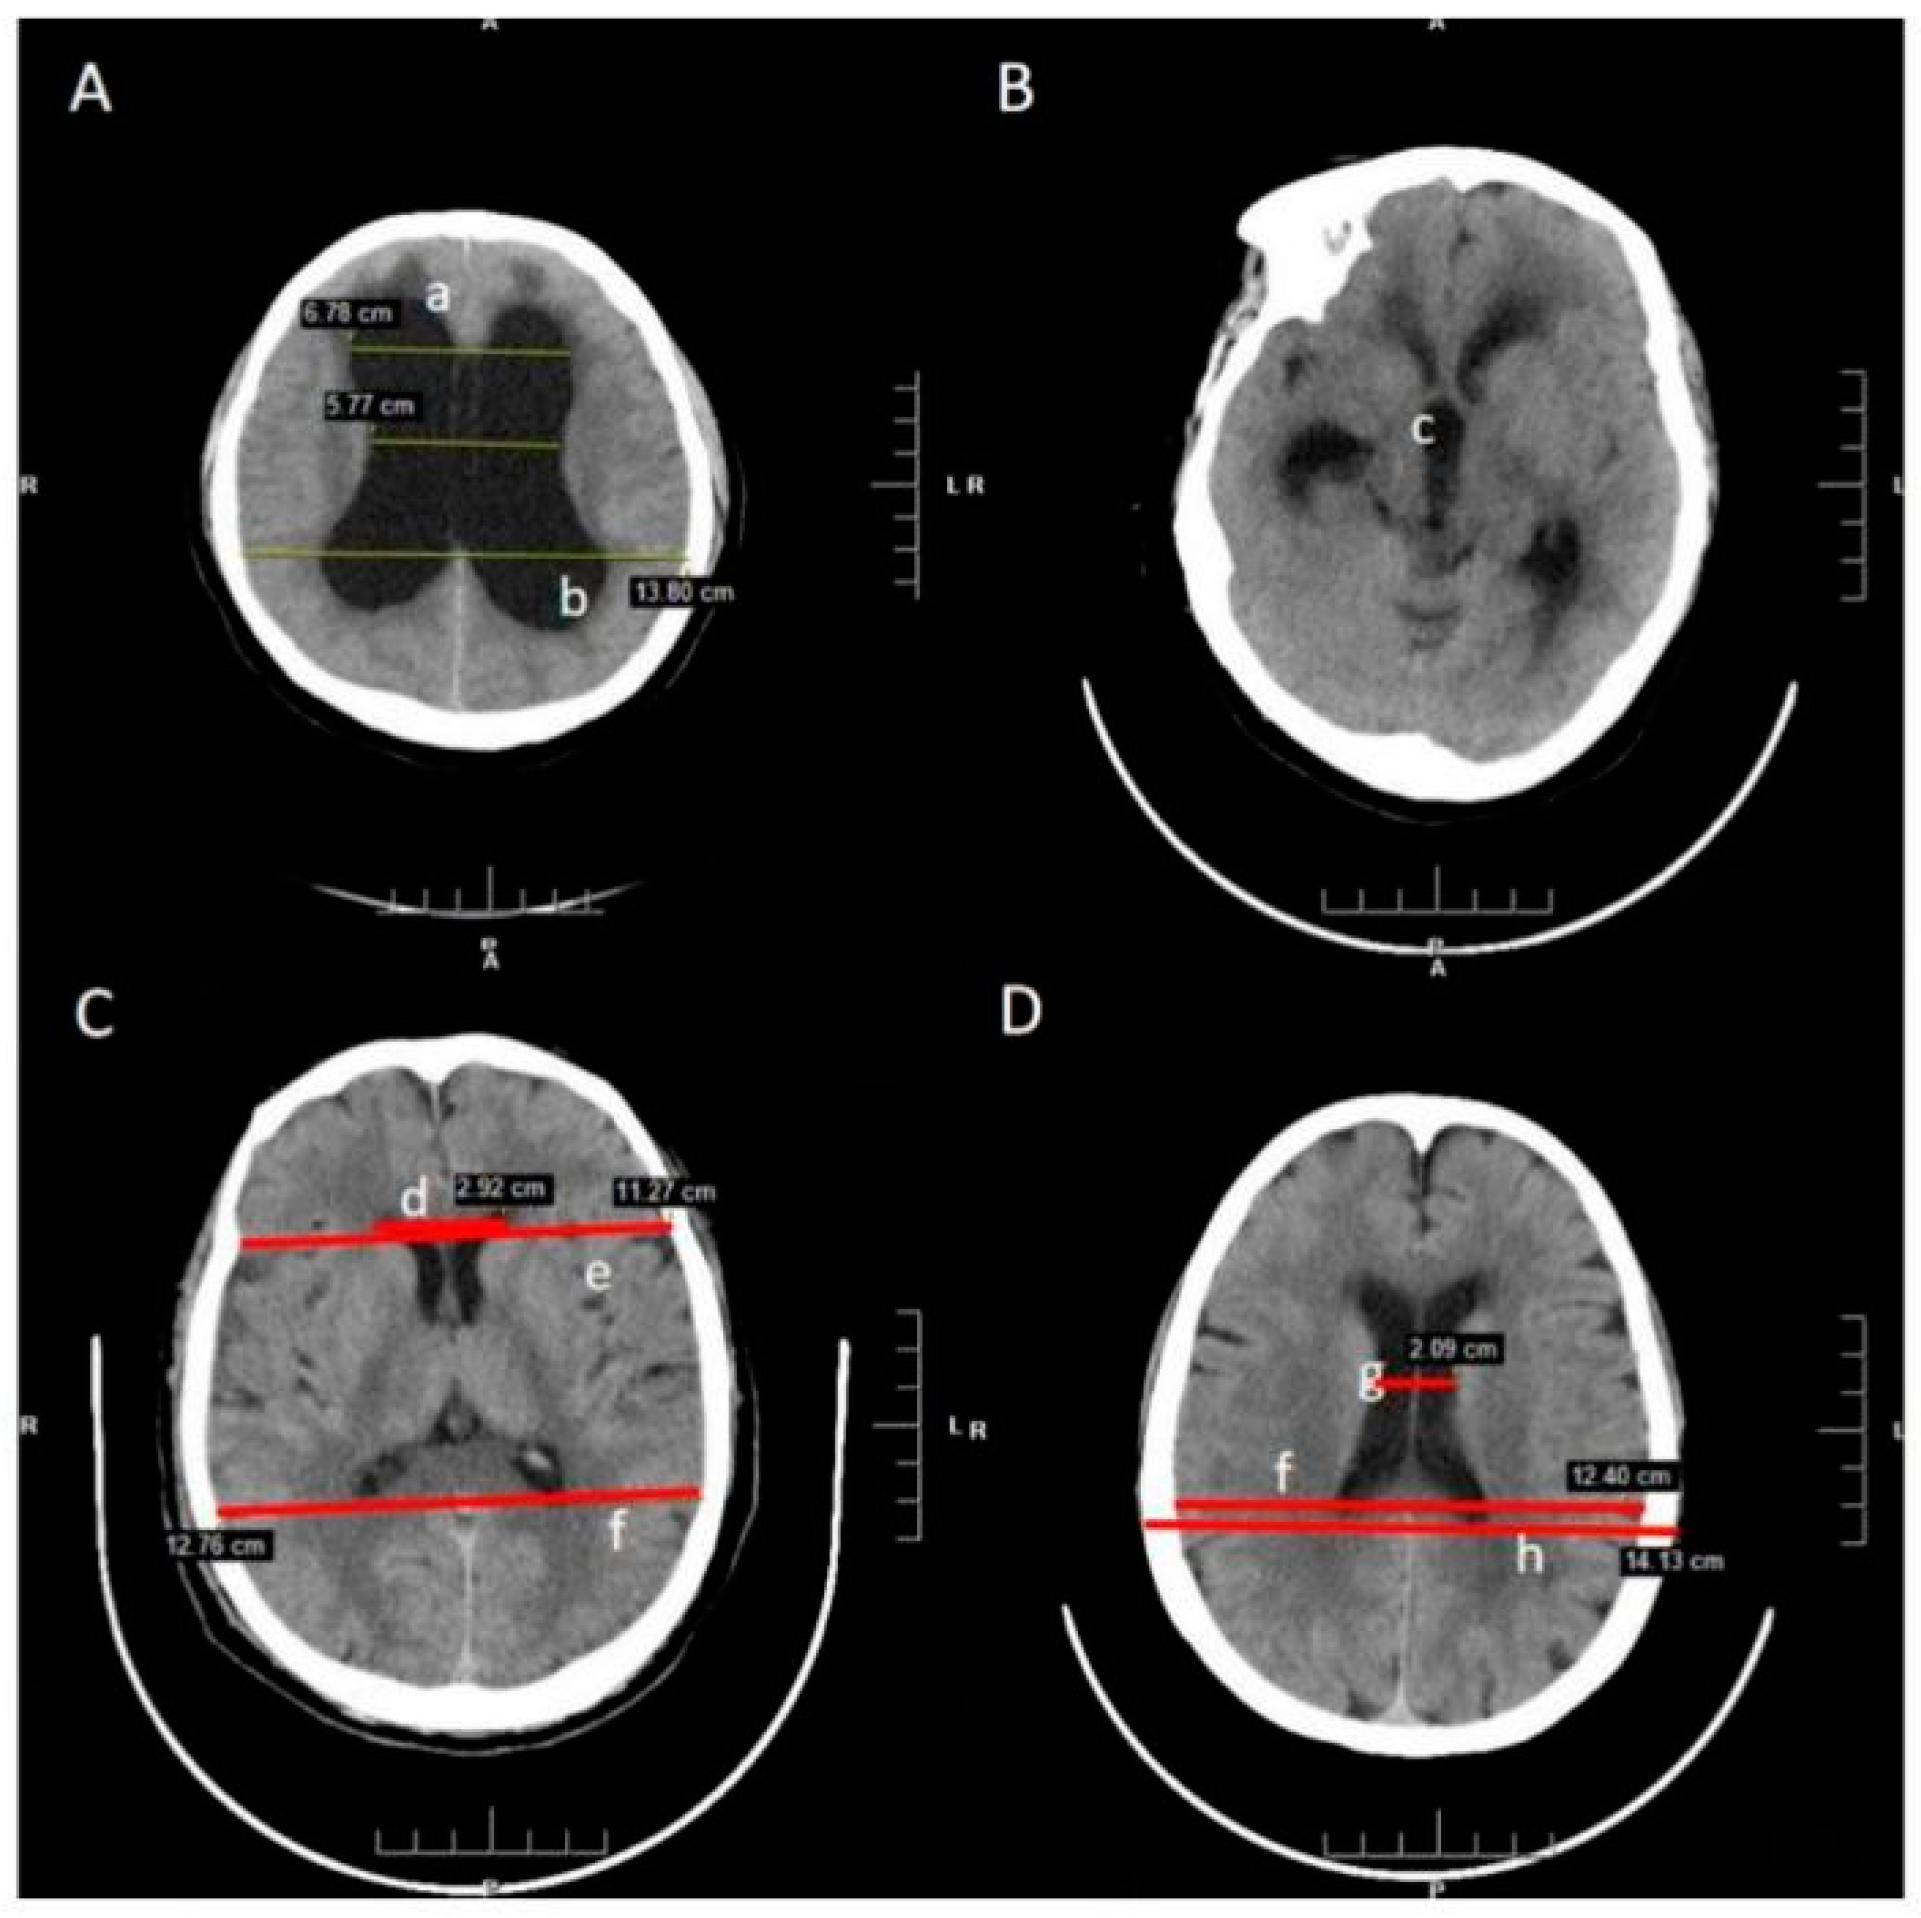

| MLL | The narrowest width between the lateral walls |

| MTD | Maximum transverse diameter of the skull |

| DSL | The internal diameter of the skull in the same line as MLL |

| BPD | Maximum width of internal diameter of the skull |

| DM | Inner diameter of the skull in the same line as FHL |

| FHL | Width of greatest span of frontal horns |

| ER = FHL/MTD (d/f) | The ratio of the transverse diameter of the anterior horns of the lateral ventricles to the internal diameter |

| CMR = MLL/BPD (g/h) | The ratio of the minimum distance between lateral walls of lateral ventricles in cella media region |

| FHR = FHL/DM (d/e) | The ratio of maximum width of the frontal horns of the lateral ventricles |